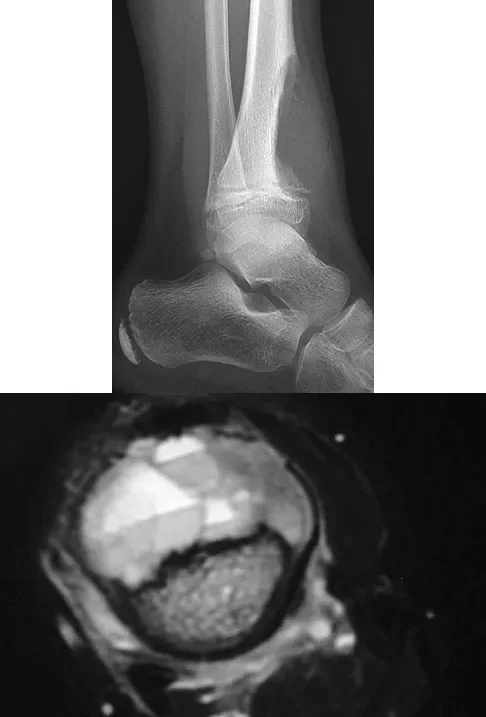

The MRI scans shown demonstrate a lipohemarthrosis in the knee. Which of the following is the most common underlying etiology for this specific MRI finding?

Explanation

Correct Answer: C

Lipohemarthrosis is characterized by the layering of fat and blood within a joint cavity. The most common cause is an intra-articular fracture, which allows marrow fat to escape into the joint space. On MRI, it typically shows a superior layer of fat, a central layer of serum, and an inferior layer of red blood cells. While an ACL tear causes a hemarthrosis, it does not typically cause a lipohemarthrosis unless accompanied by an osteochondral fracture.

A patient presents to the emergency department with acute knee swelling following a high-energy trauma. T1-weighted MRI is obtained and shown. The distinct layering effect seen in the suprapatellar pouch is most strongly associated with which of the following underlying injuries?

Correct Answer: Intra-articular fracture

The MRI scan demonstrates a lipohemarthrosis, characterized by the layering of fat, serum, and red blood cells in the joint space. The superior layer contains fat (high signal intensity on T1), the middle layer contains serum, and the dependent layer contains red blood cells. The presence of a lipohemarthrosis is highly indicative of an intra-articular fracture, which allows marrow fat to escape into the joint cavity. While ligamentous and meniscal injuries can cause a hemarthrosis, they do not typically introduce marrow fat into the joint unless accompanied by an osteochondral defect or fracture.

A patient presents with acute knee swelling following trauma. MRI scans (T1 and T2-weighted) are shown. The layering effect seen within the joint space is most strongly associated with which of the following underlying injuries?

The MRI shows lipohemarthrosis, characterized by layering of fat (superior, high signal on T1), serum (central, low signal), and red blood cells (inferior, low signal). This finding is highly indicative of an intra-articular fracture, which allows marrow fat to escape into the joint space.

A patient presents with acute knee swelling following trauma. T1- and T2-weighted MRI scans are shown, demonstrating a characteristic layering effect within the joint effusion. This finding is most strongly associated with which of the following underlying injuries?

The MRI scans demonstrate a lipohemarthrosis, characterized by the layering of fat (superiorly, high signal on T1), serum (centrally), and red blood cells (inferiorly, low signal). The most common cause of a lipohemarthrosis is an intra-articular fracture, which allows marrow fat to escape into the joint space. While an ACL tear can cause a hemarthrosis, it typically does not produce a lipohemarthrosis unless accompanied by an osteochondral fracture.